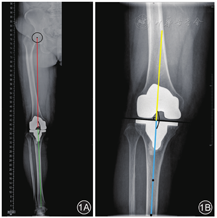

股骨机械轴:股骨头中心与股骨远端髁间窝中点连线;胫骨机械轴:胫骨嵴中点与踝关节中心连线。股骨机械轴和胫骨机械轴之间形成的内侧夹角即为下肢全长X线片下肢机械轴[5] 。见图1A。

股骨轴线:通过股骨假体表面中点做胫骨假体关节面的垂线;胫骨轴线:取胫骨假体表面远端10 cm处两侧骨皮质连线的中点,再取胫骨最远端两侧骨皮质连线的中点,两点的连线即胫骨轴线。两轴线之间形成的内侧夹角即为局部膝关节X线片下肢机械轴。见图1B。